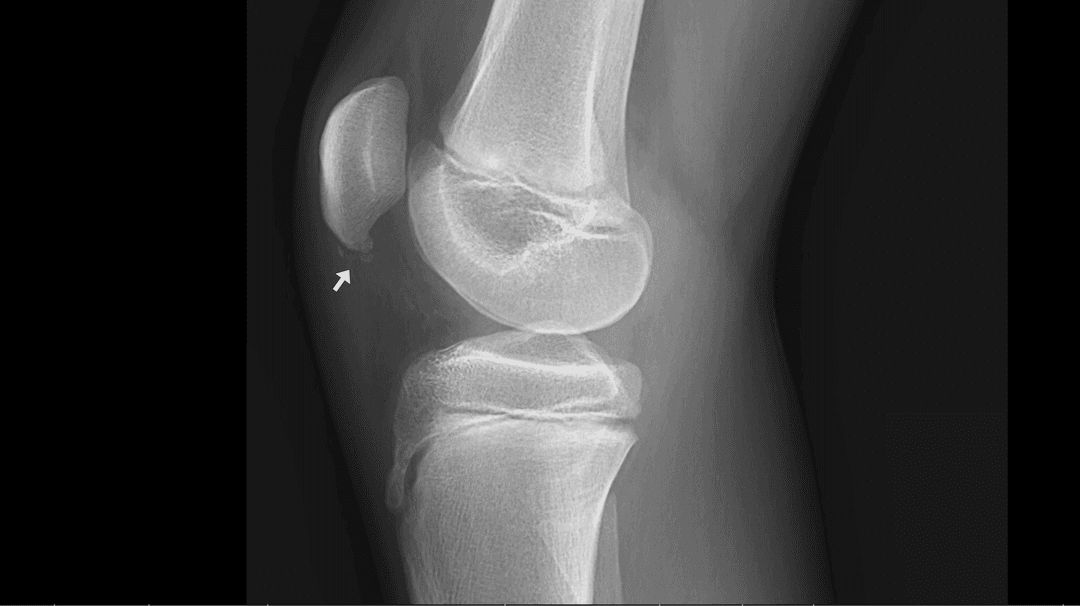

Gonalgie antérieure infra patellaire chronique bilatérale chez un adolescent de 15 ans pratique de manière intensive le basketball.

Radiographie

Calcifications irrégulières au pôle distal en lien avec une ostéochondrose de Sinding-Larsen-Johansson au Stade II de la classification radiologique de Medlar et Lyne